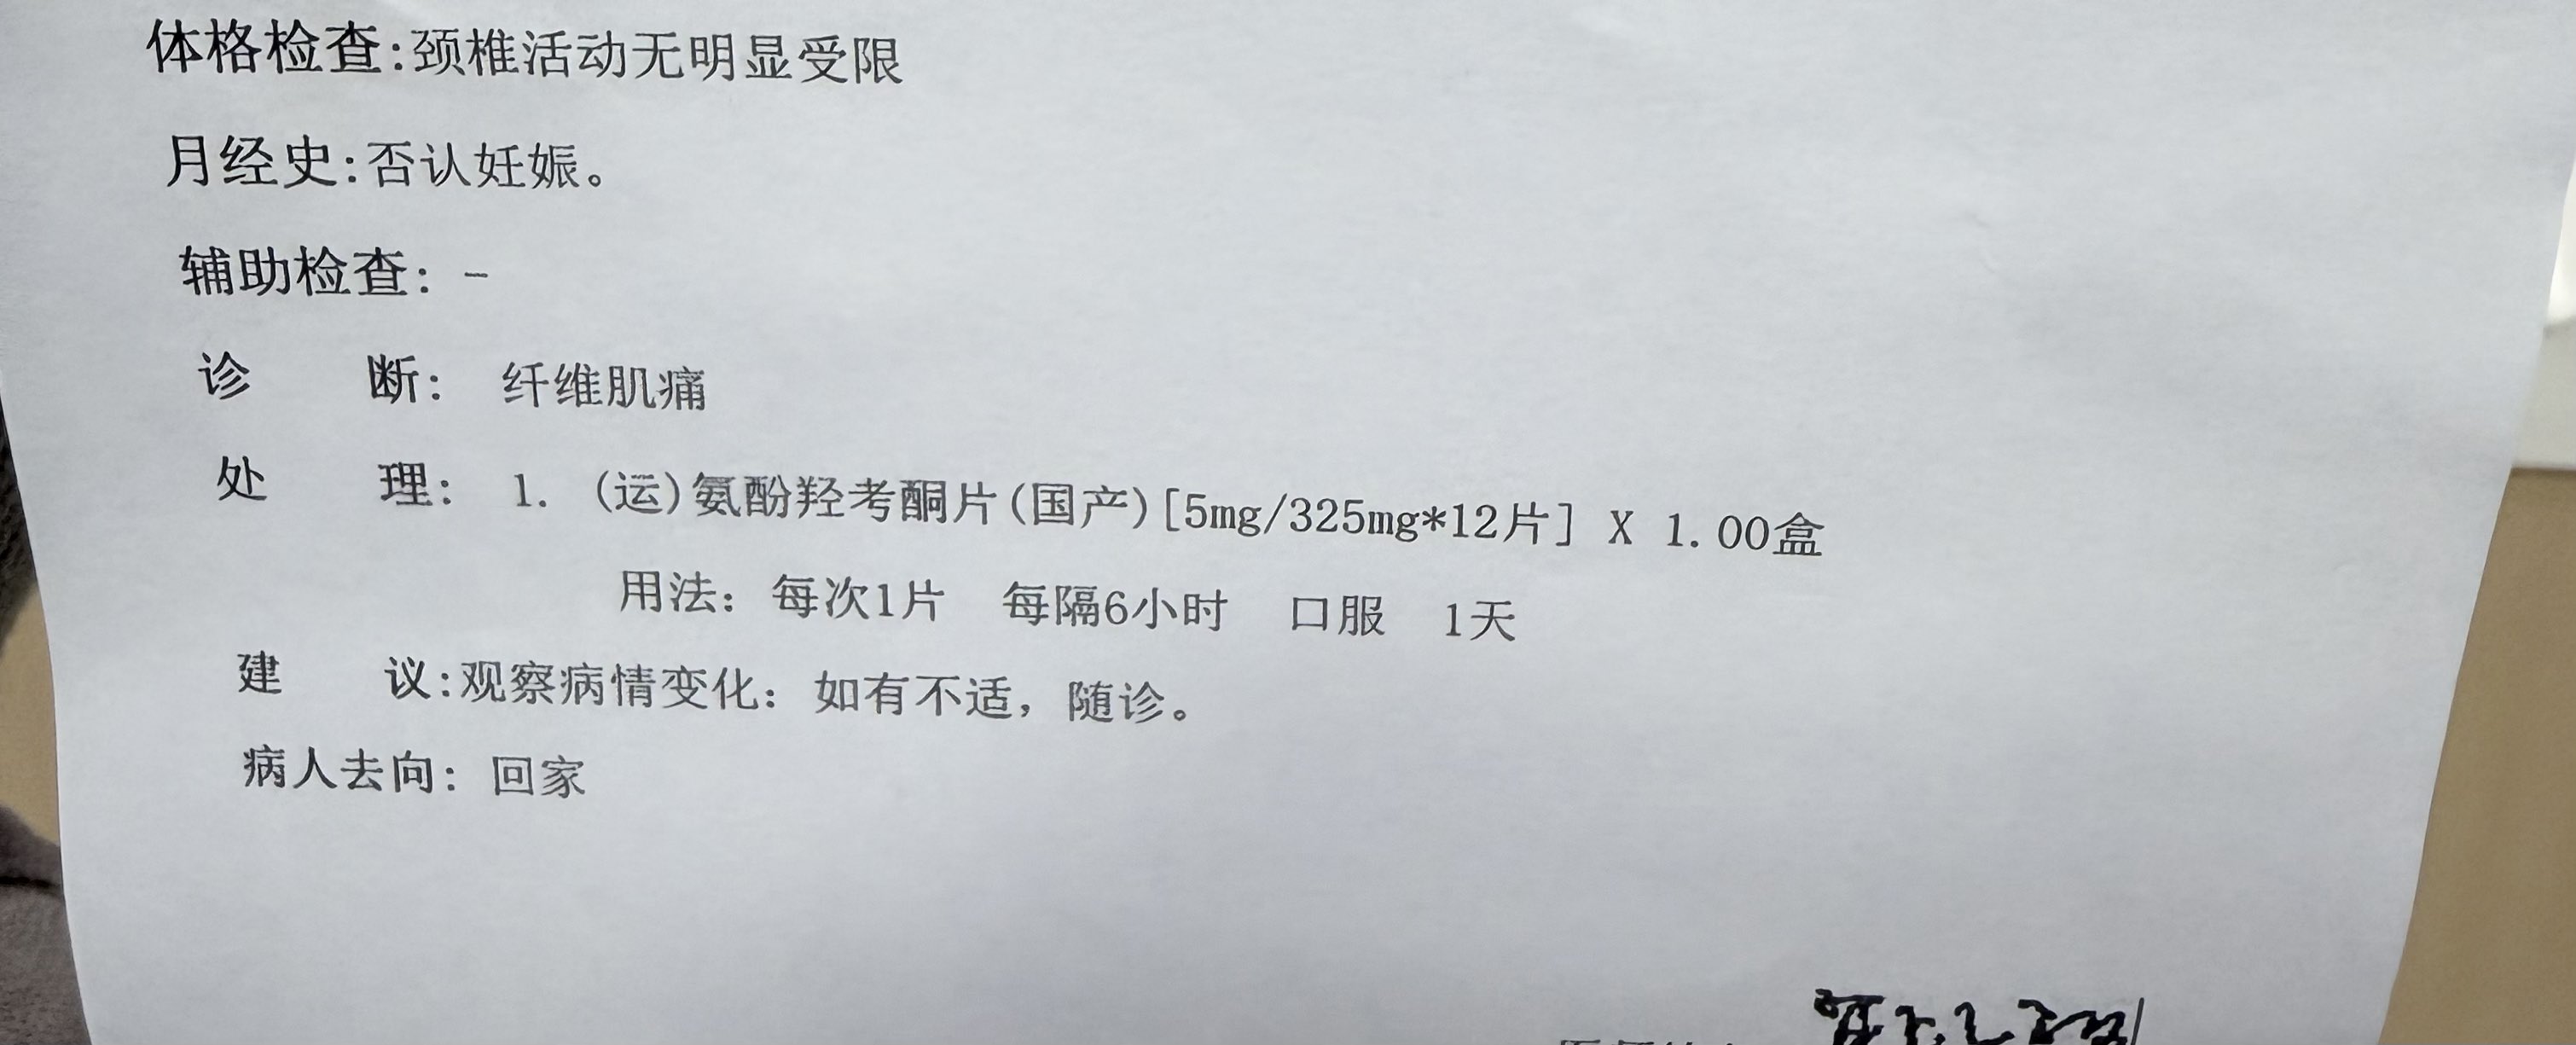

有救了..!但是和auv冲突了…cyp2d6被ban的不剩一点,吃个dxm能晕完第二天。陷入沉思…

差点开依托考昔出来,我报了一遍吃过的菜名,医生说吃没吃过抗抑郁药吃过哪些,我又报了一遍菜名,然后继续踢皮球说原发性痛经妇科比较有经验,我说妇科的方法我用不了会抑郁发作,拉扯半天终于妥协 https://t.co/IHCrUWrCjA

找值班医生护士开药,因为平常自己吃的没带过来,优先就考虑了曲马多(口服/注射),我说和我抗抑郁药cyp2d6冲突了

医:那羟考酮?(发愁)你用的药这么多怎么全是冲突 https://t.co/6fs24OppyL

炽烈已极 @AnIncandescence我说不用那么强的也可以,医问加巴喷丁?我说弱了……于是目的达成,开了pr75

2026-03-22 15:58:58 UTC

虽然我吃这点可能没什么效果,但出院的时候说不定能开医嘱开处方甚至带药,处方有希望了!

其实我还想要巴氯芬那些的肌松,到时候在哪用就都是光明正大的&药也不用藏了耶✌️